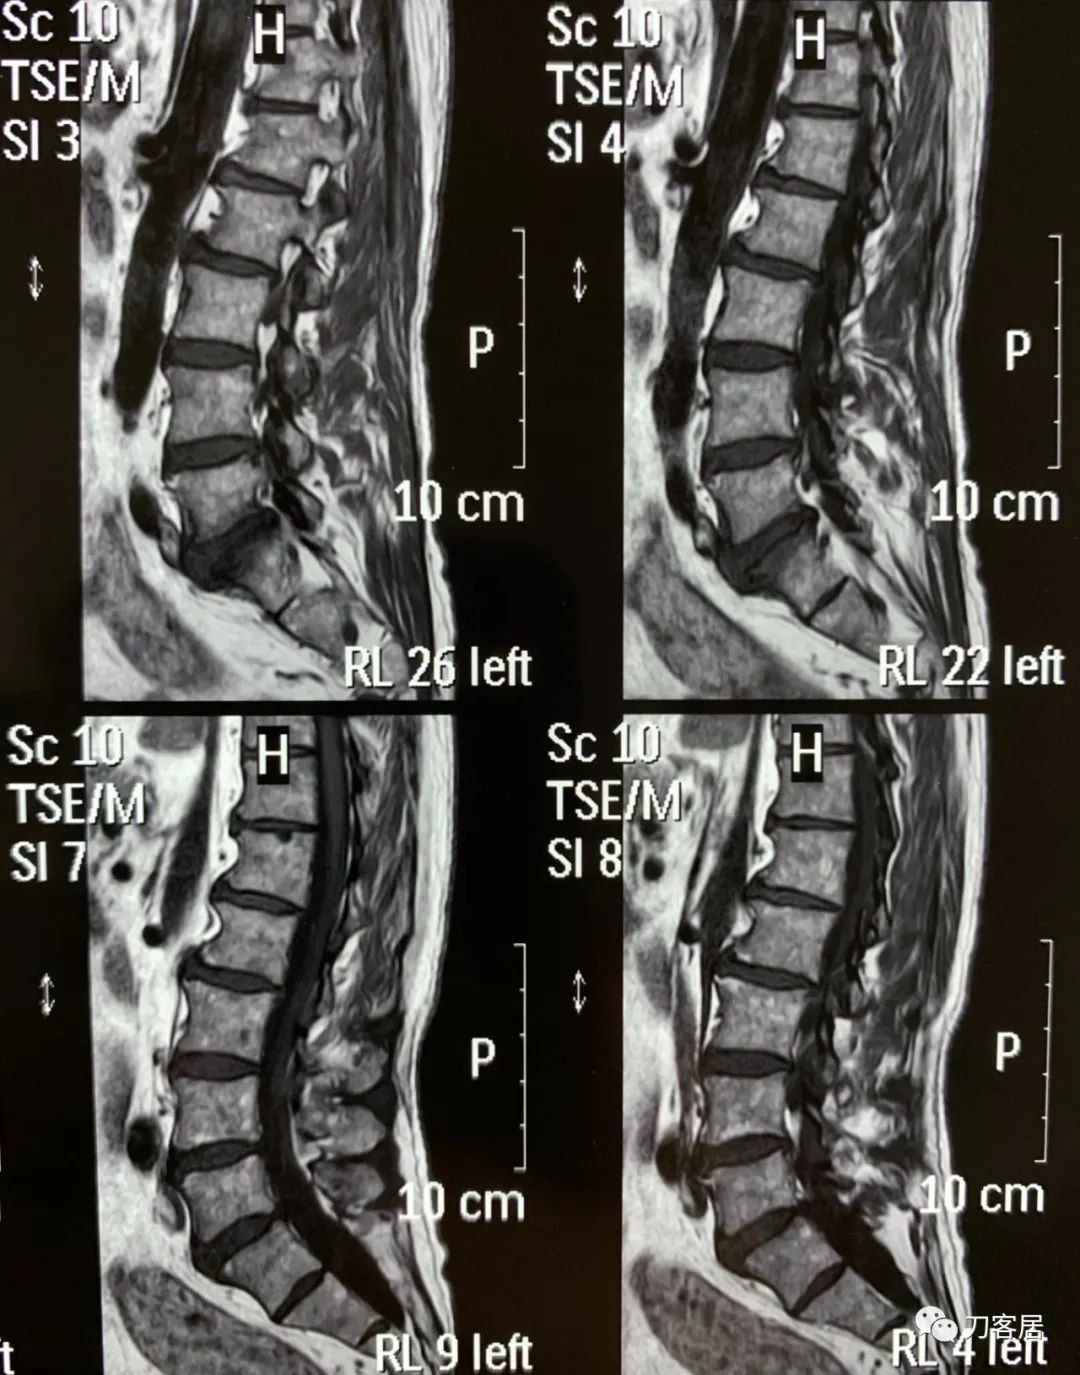

自带颈椎MRI颈5-6退变性滑脱,颈5椎体后移,不稳,但患者无明确的神经损伤表现,且保守治疗有效,暂不考虑手术治疗。腰椎MRI及CT未见严重之椎间盘突出及椎管狭窄,腰椎失稳。

图16. 20190409-QHM-C-A医院-腰椎MRI01

图17. 20190409-QHM-C-A医院-腰椎MRI02